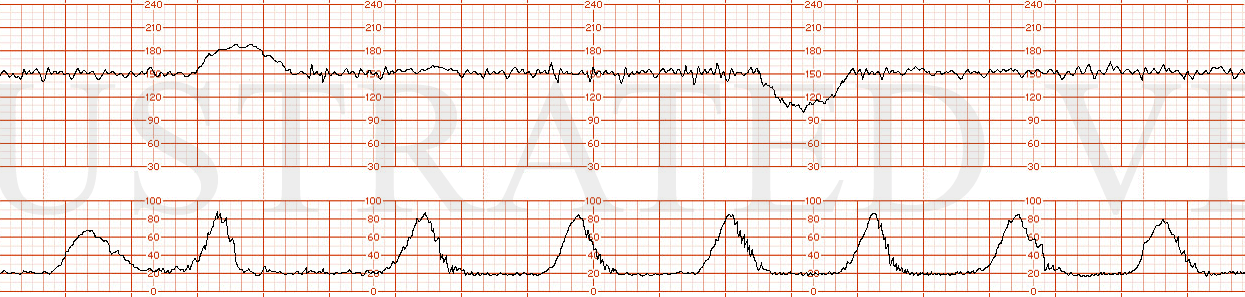

STRIP 71

1. 1st panel:

Contractions – average of 4 contractions / 10 minutes each symmetric x 60 seconds 3rd too long 30secs, 4th too long 20secs,

Baseline 1 – 145 with average variability

Decelerations 1 - none

Accelerations1 – none

2nd panel:

Contractions – 6 contractions / 10 minutes x 70 seconds with asymmetry to right i.e. 40sec after peak. (5th too long, shorten little, 8th make little longer)

Baseline2 – 150 with 3-5 bpm variability

Decelerations 2 – sporadic mild late decelerations – 10-15 bpm nadir x 1min with every 4th contraction with random nadir showing no progression in depth. (1st decel move 20-30 sec to left, 2nd decel move over the 8th contraction and make it look more gradual)

Accelerations2 – none; scalp stimulation negative response at 12 minutes into this panel. Write on strip point of scalp stim with no parallel accel.